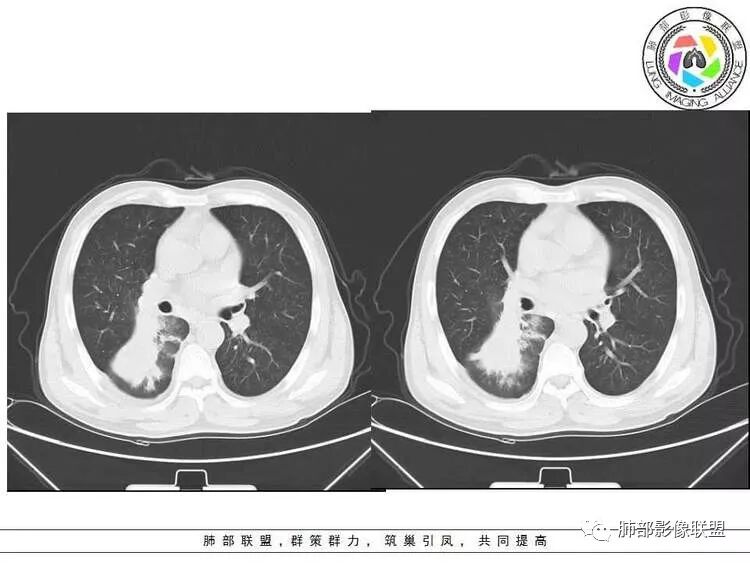

南边:紧贴着斜裂过来的一个病灶,它的特点是:外围大,内带小。它整个下叶背段体积与对侧相比稍微缩小一点,但是缩小地不是很厉害。外支朝前下走了,仔细看血管,肺动脉走行自然,直达远端。远端实变区是肉芽肿成分,稍微有一点低密度,没有明显坏死,稍微有一点点坏死。而且附近有很多卫星灶,附近很多斑片影,有一些明显有气道壁增厚,细支气管炎的特点,还有就是下叶其他段很多斑片状影。换个角度,第一如果是肺癌,刚才看到PET-CT提示肺癌伴阻塞性肺炎,这个是不符合的。第二如果是肺癌阻塞性肺炎,近端血管肺动脉走行不会那么自然集聚的,这个是不符合的。理由是:如果这个病灶是肺癌,那么明显属于中央型肺癌,中央型肺癌的特点是近端大,远端小,近端是一个肿块,远端阻塞,远端阻塞是阻塞性炎症或者不张,它应该体积缩小,斑片状实变,不会这么密实。刚才有老师提到支气管,这个片有缺陷的地方,给的图像好像那层,如果把其他图像拿开再重叠一下。

南边:你就发现外侧支气管朝下走的分支非常自然,通畅的。

南边:这个肺门区,11区和7区都有一些淋巴结,淋巴结的形态不是类圆形,而是梭形的。这个病灶给的图比较少,个人倾向,第一强化非常均匀,肉芽肿性病变;第二,里面血管走行非常自然,远端大近端小,倾向炎性,特别是下面还有斑片状影,非阻塞远端,支气管远端病灶下叶背段,其他段也有,所以我倾向炎性;另外,它里面整个走行符合支气管树爬行征,我倾向结核可能,首先我定在炎性,其次有没有结核的可能。

右肺下叶背断肿块,外围大,内带相对狭长         远端有膨隆,边缘模糊、凹凸不平         血管走形自然,病灶近端支气管通畅,沿支气管树蔓延         周边有多发病灶,多为磨玻璃密度且边界不清。